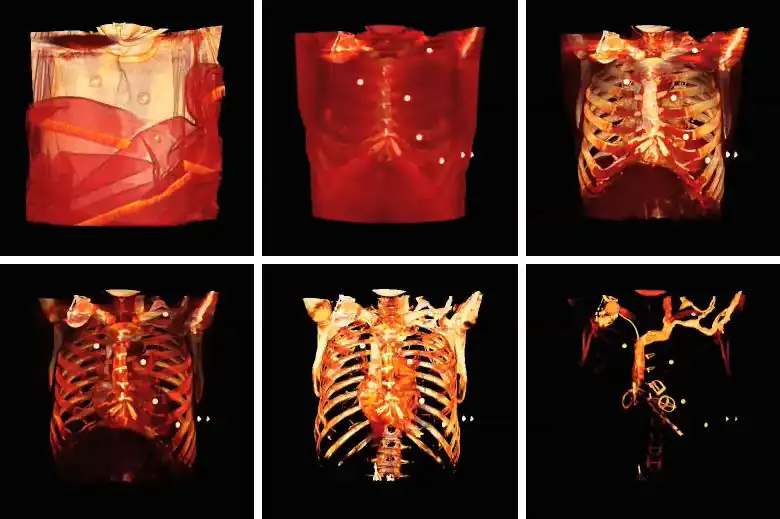

Surface rendering is also referred to as Shaded Surface Display (SSD) and involves generating surfaces from regions with similar voxel values in the 3D data as illustrated by the SPECT lung-perfusion scan shown in the left panel below:

The process involves the display of surfaces which might potentially exist within the 3D voxel data on the basis that the edges of objects can be expected to have similar voxel values. One approach is to use a grey-level thresholding technique where voxels are extracted once a threshold value is encountered in the line of the projection – see the following diagram. Triangles are then used to tesselate the extracted voxels, as shown in the right panel of the figure above – and the triangles are filled using a constant value with shading applied on the basis of simulating the effects of a fixed virtual light source – as shown in the left panel above.

An opacity table can be applied to the results so that surfaces from internal features can also be visualized. As an example, two surfaces have been identified in the following image from the CT scan where voxel values from bone surfaces are coded in an opaque yellow colour and tissue surfaces in a transparent shade of red.

A second example of using an opacity table is shown in the following figure. Here, axial CT data from the patient's airways have been segmented using a region growth technique and the result processed using surface rendering, with full opacity as shown in the left panel and with a reduced opacity (30%) as shown in the right panel:

Notice that internal features of each lung can be discerned when the opacity is reduced. Notice also that continued viewing of this type of transparency display can generate apparent reversal of the image rotation, similar to that noted for the 3D MIPs above. One method of overcoming this type of problem is to segment each lung, for instance. and to blend the results, as illustrated in the following figure: